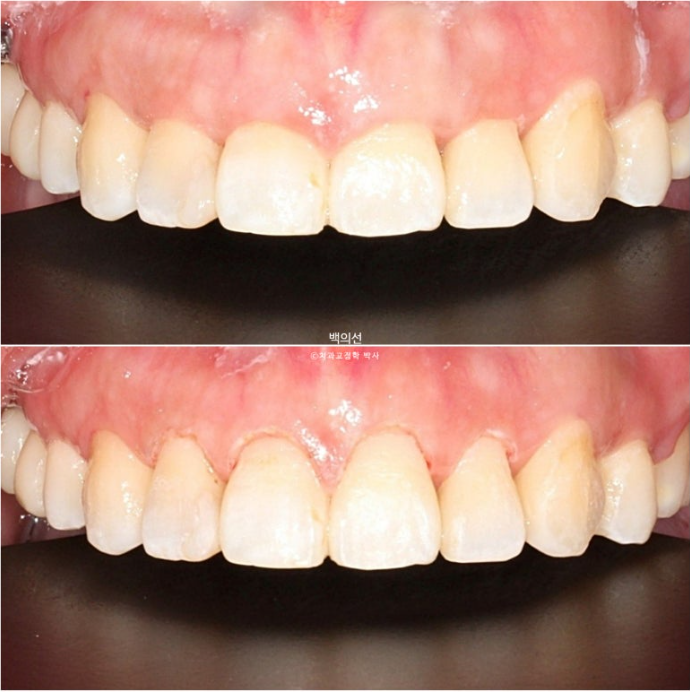

짧은 앞니 길이를 회복하고자 위 앞니 4개에 잇몸성형을 합니다.

25.06

잇몸성형 직후 모습입니다. 잇몸성형은 <성형> 글자가 들어가니 무섭게 느껴지지만, 실제로는 피가 나거나 하지 않습니다.

잇몸성형 후 일주일간의 회복기간을 거친 후 모습입니다.